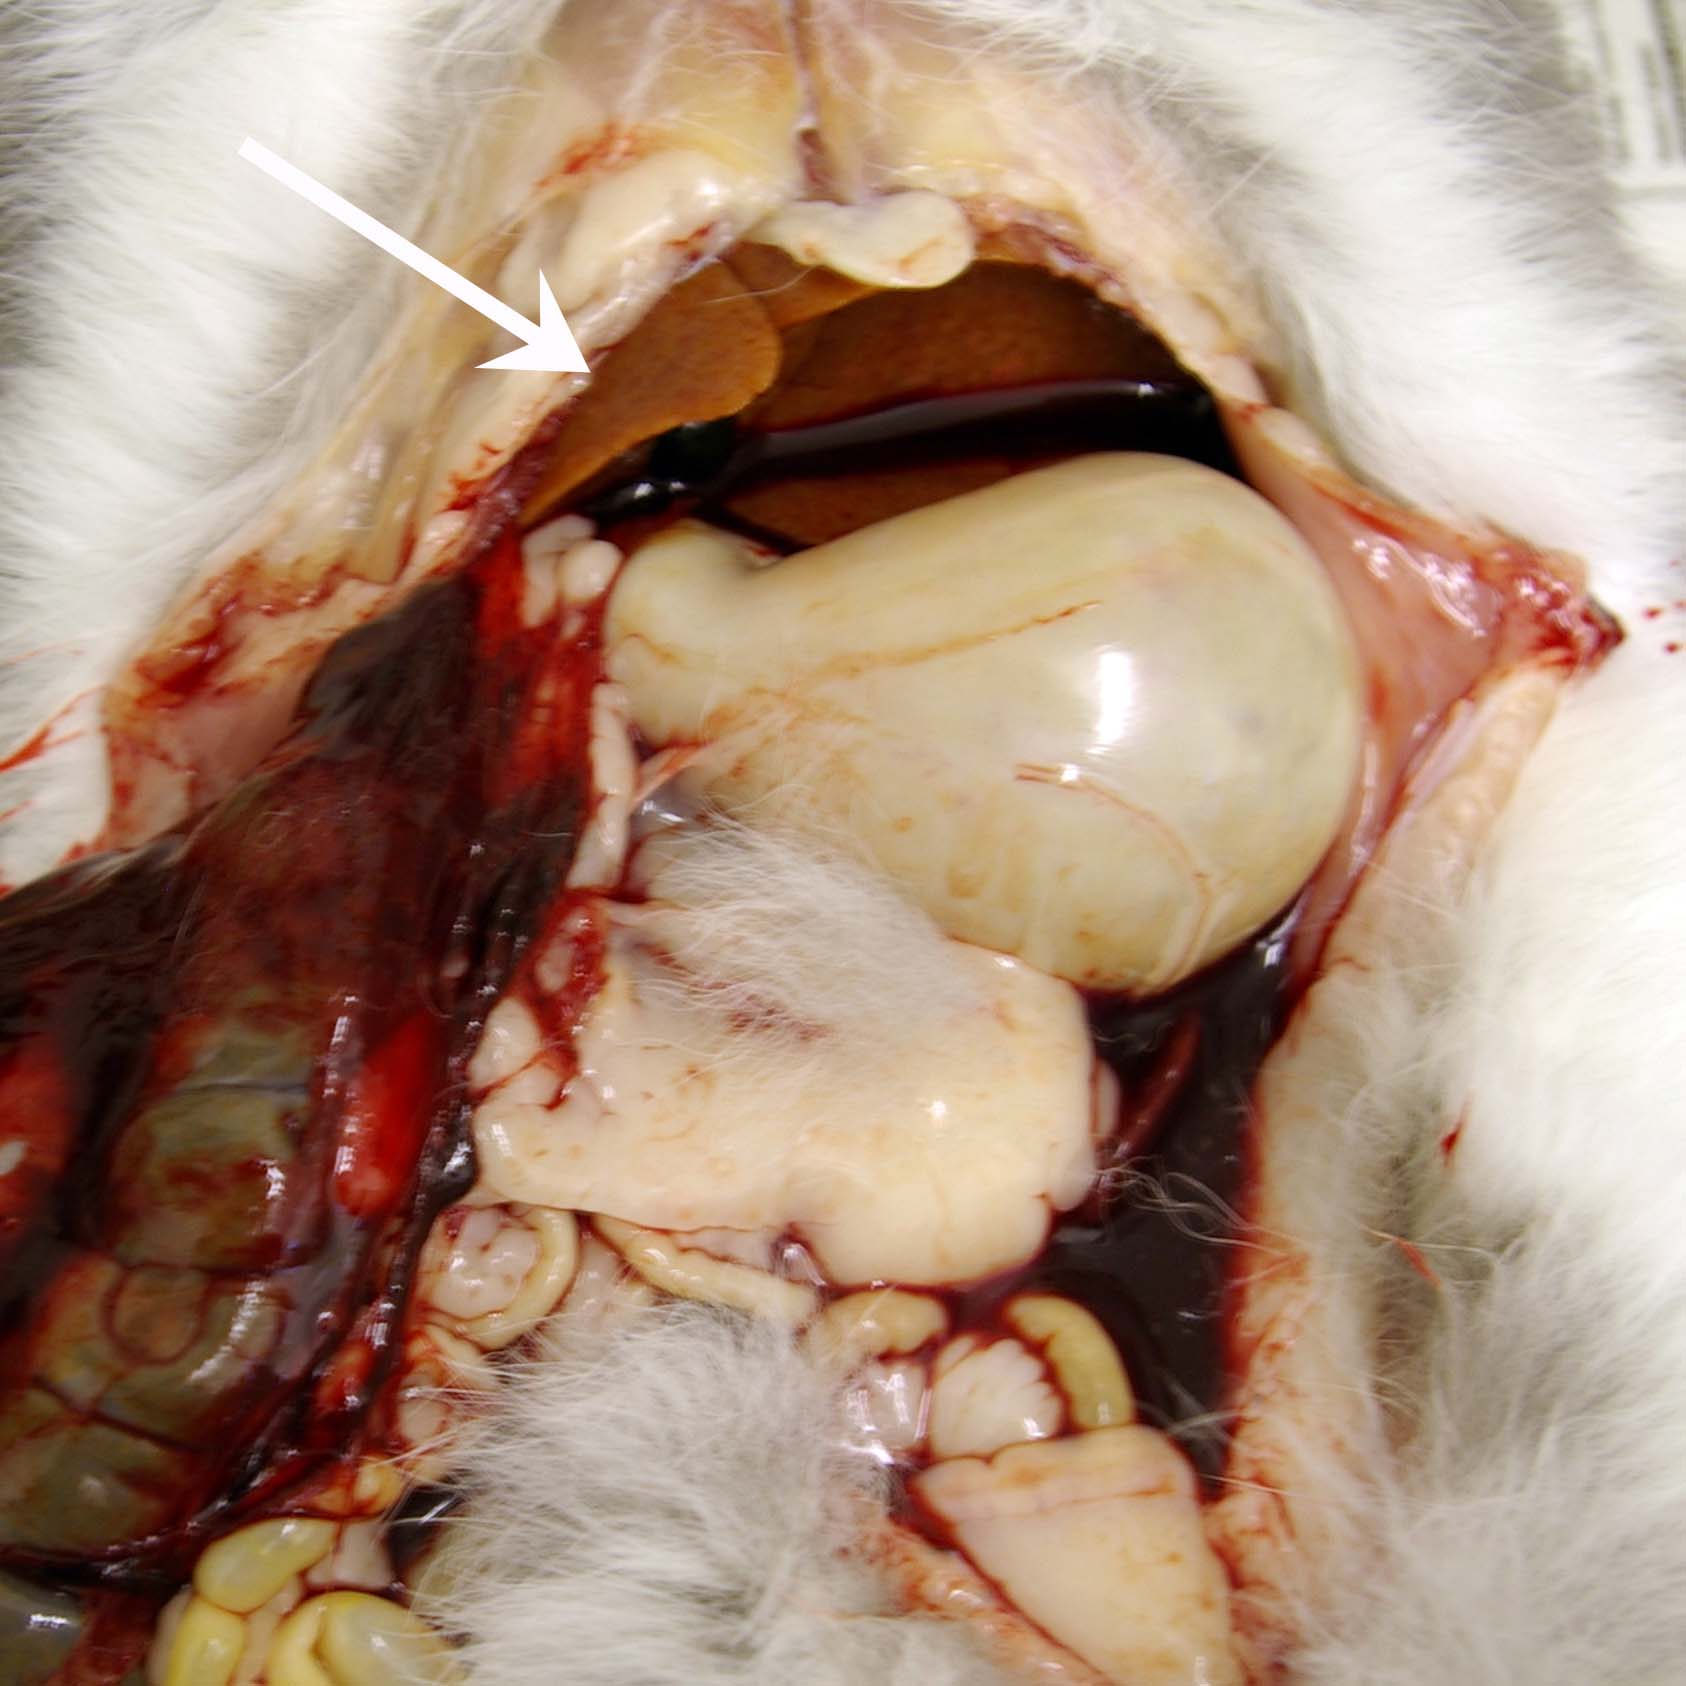

Hepatic lipidosis- ruptured liver

Abdominal haemorrhage was found in this rabbit that died on the way home after examination and treatment for anorexia. During the consultation. the rabbit struggled as the owner was returning it to its carrier. Unfortunately the rabbit escaped and fell from the consulting table. Post-mortem examination showed that abdominal haemorrhage from a ruptured liver was the cause of death. The liver was pale (arrow). Histopathology confirmed the presence of heaptic lipidosis.